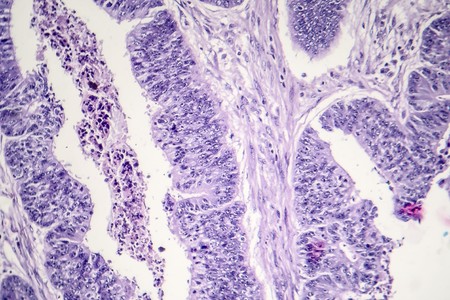

Histopathology of intestinal adenoma, light micrograph, photo under microscope